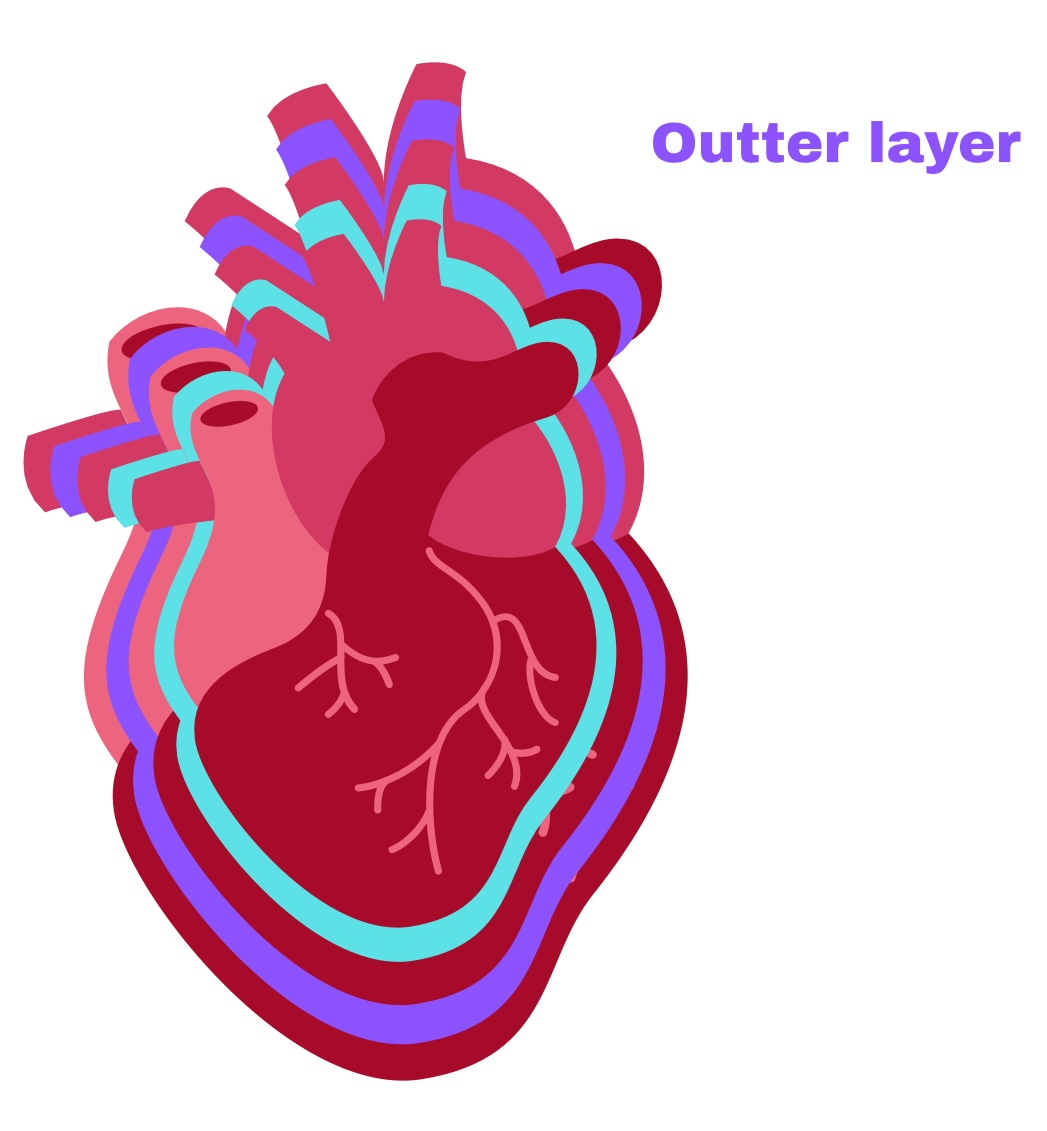

Partial Pericardium

Outer layer

Visceral Pericardium

Deep layer (surface of organ)